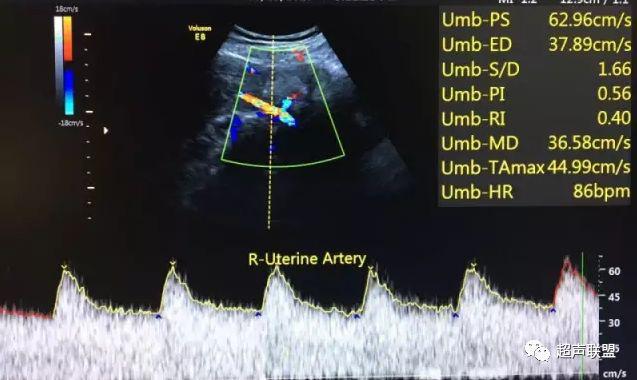

5 子宫动脉血流测定

正常妊娠时血流速度增加,血流阻力降落。缺氧早期的血流再分配,子宫动脉血流RI、PI值增加,阻力指数(RI)>0.57,子宫动脉血流频谱出现切迹。

3、子宫动脉标准:孕26或27周后,子宫动脉S/D>2.7,(RI)>0.57,有舒张早期切迹;

图7 正常中孕期子宫动脉频谱

图8 胎儿宫内缺氧,子宫动脉舒张早期可见切迹